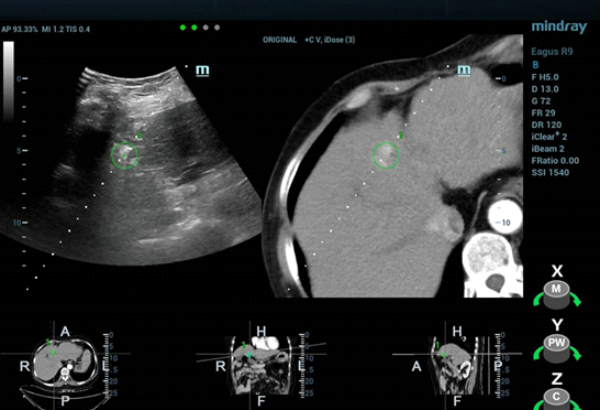

The patient was scheduled for ultrasound-guided microwave ablation (MWA), however, as the lesion could not be seen on conventional ultrasound, fusion imaging combining ultrasound imaging and contrast-enhanced CT (Clip 1, Figs. 4-7) was used to ensure accurate positioning of the microwave antenna.

The tumor was isoechoic and could not be clearly displayed using 2D grayscale ultrasound, therefore using conventional ultrasound guidance alone could result in inaccurate positioning and incomplete ablation. However, Fusion Imaging combining real-time ultrasound with the contrast-enhanced CT dataset allowed for accurate antenna positioning and successful treatment of the lesion by percutaneous MWA. CEUS was used pre-procedure to confirm tumor location and post-procedure to evaluate the ablation zone and ensure the efficacy of the treatment.